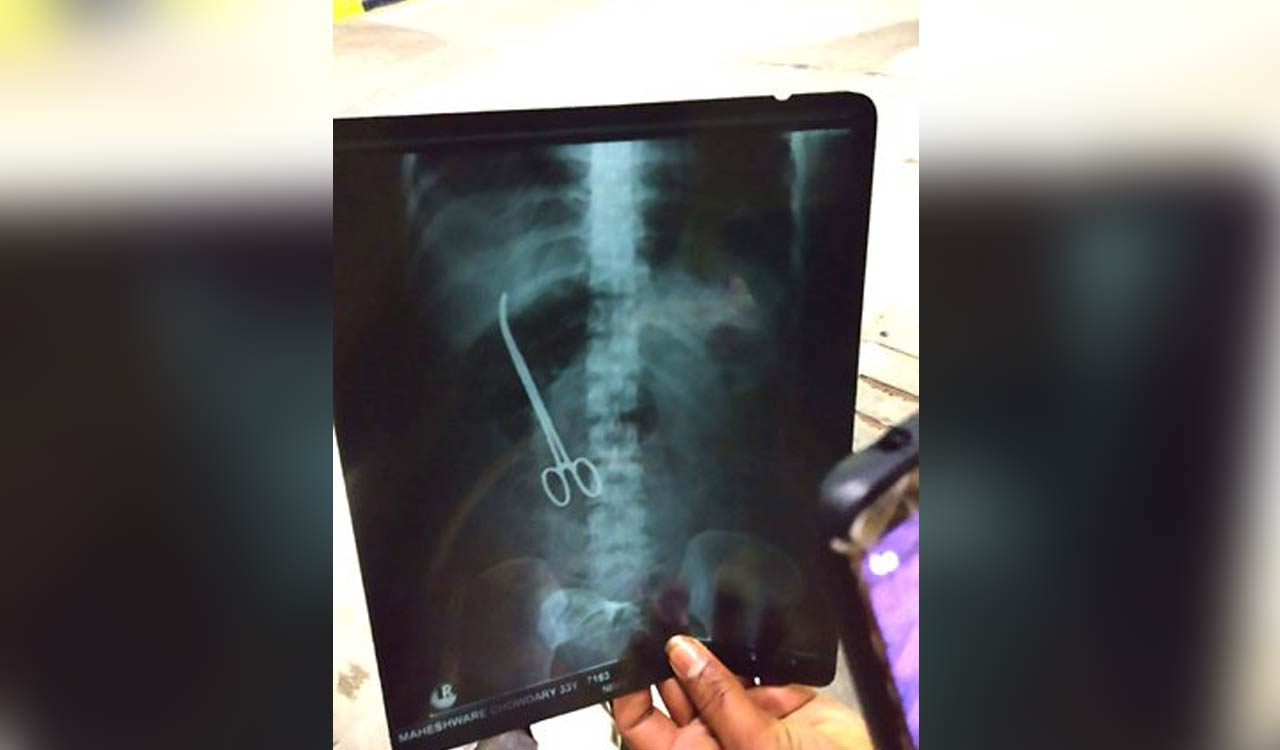

In a startling case of alleged medical negligence, doctors reportedly left a pair of forceps inside a woman's stomach following her cesarean delivery at a government hospital in Eluru.

Vijayawada: In a shocking incident of medical negligence, doctors allegedly left forceps in a woman’s stomach after her cesarean delivery at a government-hospital at Eluru in Andhra Pradesh.

Nearly three months after the doctors left the artery forceps, the incident came to light when a scan was done at Vijayawada Government Hospital, where the woman was referred to after she complained of persistent pain.

Artery forceps are used to control bleeding from blood vessels by clamping the artery. However, the doctor who performed the procedure forgot to remove the same.

Various tests, including x-ray were conducted, at the Vijayawada Hospital and to their utter shock, the x-ray showed forceps in her stomach. However, the issue came to light when a hospital employee posted a photo of the x-ray on his social media accounts.

The superintendent said a senior gynecologist had performed the cesarean but unfortunately artery forceps was left. He said when the woman came to the hospital on August 8, her condition was serious.

He said that the doctors at Vijayawada Hospital have removed the forceps and the woman’s condition is stable.